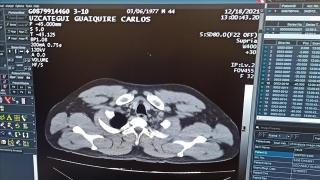

Havalimanında rahatsızlanan yolcunun midesinden 12 kapsül kokain çıkarıldı

İstanbul Havalimanı'ndaki sağlık ekiplerinin ilk müdahalesinin ardından kaldırıldığı hastanede mide ve bağırsaklarındaki kapsüller ameliyatla alınan Venezuela uyruklu şüpheli tutuklandı.

03 Ocak 2022, Pazartesi - 12:16